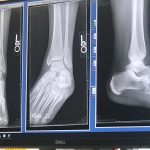

Week 6: Working with a broken ankle

This week was full of highs and lows. I was thrilled to learn that my fractures healed and my cast was coming off. Sitting in the doctor’s office, I imagined my beach walks, cooking in the kitchen, walking to the bathroom, standing in the shower, and wearing PANTS. As I left in my new boot,…